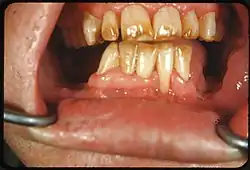

Tooth discoloration

Tooth discoloration is abnormal tooth color, hue or translucency.[1] External discoloration is accumulation of stains on the tooth surface. Internal discoloration is due to absorption of pigment particles into tooth structure.[2][3] Sometimes there are several different co-existent factors responsible for discoloration.[4]

Extrinsic discoloration

Extrinsic discolorations are common and have many different causes.[10] The same range of factors are capable of staining the surface of restorations (e.g., composite fillings, porcelain crowns).[10] Some extrinsic discolorations that are allowed to remain for a long time may become intrinsic.[11]

- Tobacco: Tar in smoke from tobacco products (and also smokeless tobacco products) tends to form a yellow-brown-black stain around the necks of the teeth above the gumline.[12]